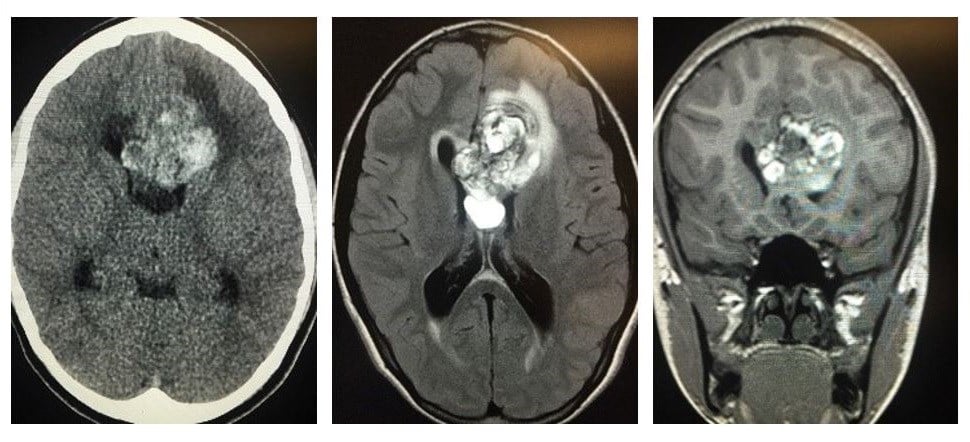

Cerebral cavernous malformations (CCM) is a rare disease that causes anomalies in tiny capillaries that transport blood throughout the brain. The disease manifests as irregularities that resemble raspberries, most often in the brain, that can lead to hemorrhage, stroke and seizures in afflicted individuals. The disease involves defects in one of three CCM genes (CCM1, CCM2, or CCM3) and affects nearly one in six thousand people. Currently, there is no clinically approved therapy to treat this disease; patients rely on invasive brain surgery for treatment, but some extreme forms cannot be treated surgically.